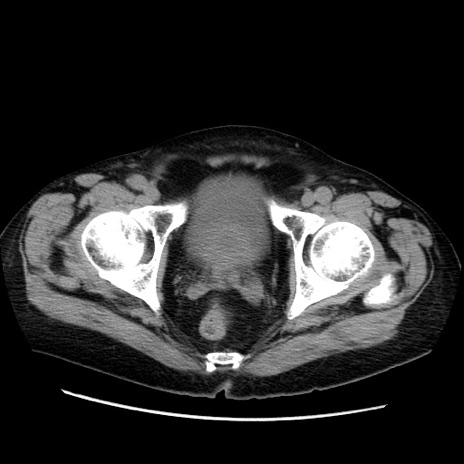

症例21(横断像)

【症例】70歳代男性

【主訴】腹痛

【現病歴】肝硬変・肝細胞癌にてかかりつけの方。約9時間前に食後より腹痛出現。症状が徐々に増悪し、嘔吐出現したため来院。

【既往歴】肝硬変、肝細胞癌(RFA、TACE後)

【身体所見】意識清明、表情苦悶様、BT 36℃、BP 129/78mmHg、P 88bpm、SpO2 97%(RA)、右上腹部から心窩部にかけて圧痛あり、反跳痛なし、筋性防御あり。

【データ】WBC 5800、CRP 0.16